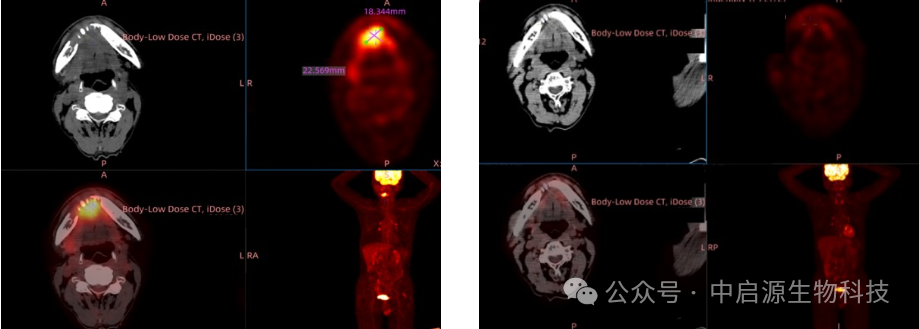

患者治疗前后PET-CT影像对比

治疗初期,李先生经历了轻微的寒颤和发热,这是细胞因子释放综合征的正常表现。经过专业处理,症状迅速缓解。治疗3周后,病灶开始明显缩小,肿瘤的扩散势头被遏制。到了第9周,影像学检查显示肿瘤完全消退,这一结果不仅超出了李先生的预期,也令医疗团队惊喜不已。